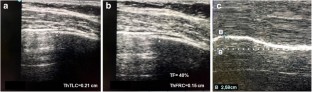

Fig. 1

Fig. 2

Fig. 3

Fig. 4

Fig. 5

Fig. 6

Fig. 7